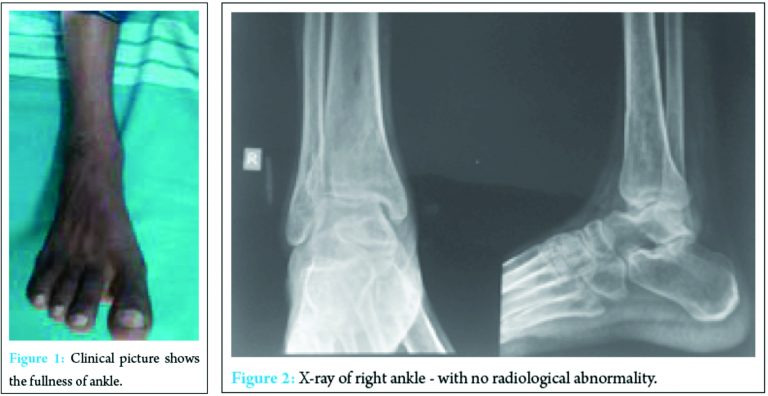

A 30-year-old male presented with a 1-year history of right ankle pain and swelling. He denied any history of recent infection but had had recurrent ankle pain that had been treated accordingly. When he visited our outpatient clinic, he was afebrile but had fullness of the right ankle when compared to the unaffected side (Fig. 1).There was no skin lesion, and the right ankle had almost a full range of motion except terminal restriction of dorsiflexion. Radiographs of the ankle showed apparently normal tibiotalar joint in comparison to the contralateral side (Fig. 2).

We suspected osteochondral injury of the talus and advised magnetic resonance imaging (MRI) and it showed lesions over the tibiotalar joint with joint effusion and cartilage destruction of the ankle joint (Fig. 3). On admission, laboratory findings included a white blood cell count with normal values. The erythrocyte sedimentation rate was 30 mm/h and C-reactive protein was slightly elevated. Rest all laboratory investigations were normal. In view of long-standing symptoms and MRI findings, inflammatory/pyogenic arthritis or neoplasm like osteoid osteoma of talus was suspected. With the patient in a supine position, under spinal anesthesia, the tibiotalar joint was visualized with an arthroscope after placing two standard portals. Arthroscopy was preferred because it is minimal invasive and was ideal to get tissue of interest for further investigation. Whole articular cartilage has already destroyed with lesion in the distal tibia and talus (Fig. 4).